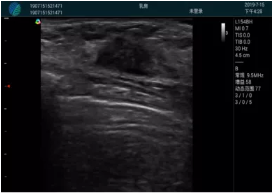

M20實(shí)時(shí)引導(dǎo):向包塊后方間隙注射利多卡因

清晰顯示腺體內(nèi)低回聲快影,邊界清晰,包膜較光滑

確定進(jìn)針路徑并實(shí)時(shí)監(jiān)測(cè)抽吸針與腫塊位置關(guān)系

抽吸針進(jìn)入腫塊內(nèi)部進(jìn)行旋切

抽吸過(guò)程中可見(jiàn)腫塊明顯縮小,并根據(jù)腫塊位置改變針道位置

抽吸旋切后再進(jìn)行超聲復(fù)查,原腫塊區(qū)域未見(jiàn)殘留組織及出血

超聲引導(dǎo)下抽吸旋切取出的腫塊組織